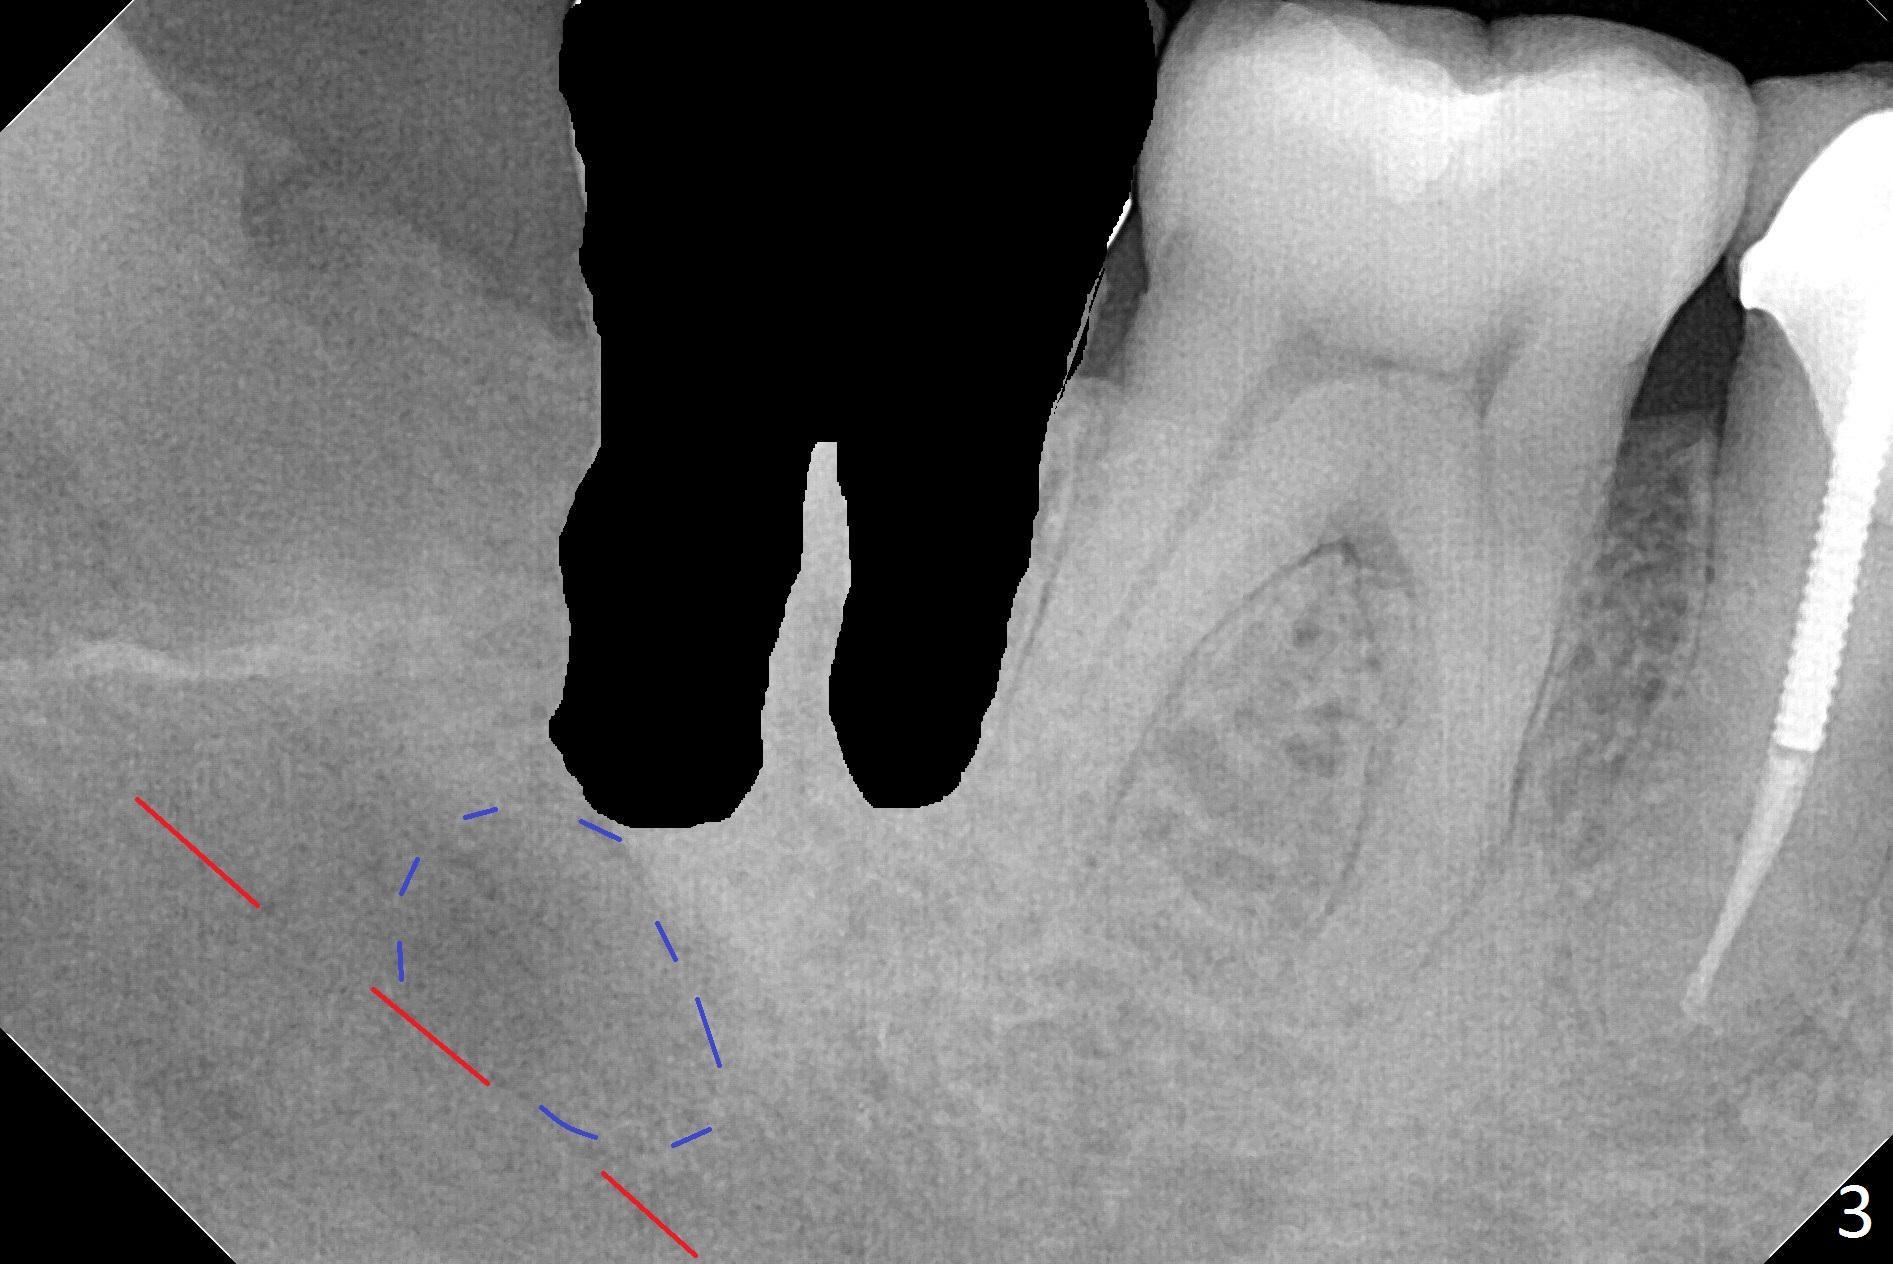

Abscess from #32 or 31?

A 45-year-old woman presents to clinic with swelling and pain from the lower right posterior region. The tooth #32 is fully bony impacted. The distolingual gingiva of #31 is erythematous with deep pocket. The tooth is sensitive to percussion. Preop panoramic X-ray shows a radiolucent lesion between #31 and #32 (Fig.1 blue dashed line). Initial impression is infection from #32. Extraction of the latter turns out to be difficult. Purulent discharge is coming from underneath the coronal portion of the tooth. Curettage of the radiolucent lesion leads to hemorrhage. The curettage is not aggressive because of the underlying Inferior Alveolar Canal (red dashed line). Following copious irrigation, a 10x20 mm Osteogen plug is inserted into the socket with incision closure. Postop PA reveals that the roots the teeth #31 and 30 approximate to each other (Fig.2 R). In case the tooth #31 needs to be removed (Fig.3 black area), osteotomy for immediate implant will be established in the middle of the septal stump (Fig.5 red arrow) after removal of the coronal septum (Fig.4). CBCT may be necessary for determination of the osteotomy depth.